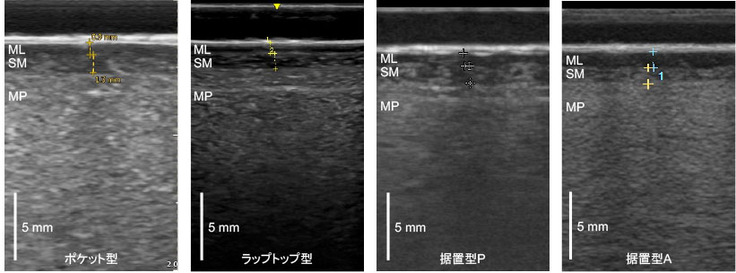

模擬舌癌ファントム最終版の検討を行っています

歯科口腔外科の先生方への口腔内超音波診断装置の貸与ならびに口腔内走査トレーニングと並行して、模擬舌癌ファントムの改善を行っています。京都科学社様にお願いしていたファントムのサンプルが最終版となり、手持ちの様々な超音波診断装置でその性能を評価してみましたが、かなり良好な結果となっています。詳細は論文にて公表いたします。

ML: 模擬粘膜上皮層、SM: 模擬粘膜下層、MP: 模擬筋層